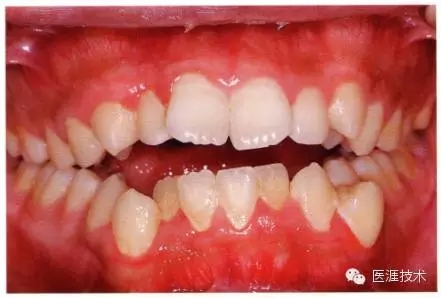

22歲男性牙齦炎的臨床圖像

640.webp (11).jpg

22歲男性,抽煙(1天約15根,煙齡5年)。刷牙狀態(tài)不佳。抽煙者特有的纖維性牙齦,未見發(fā)紅、腫脹。探針觸診,所有部位均出血。X線牙片未見骨吸收,診斷為牙齦炎。